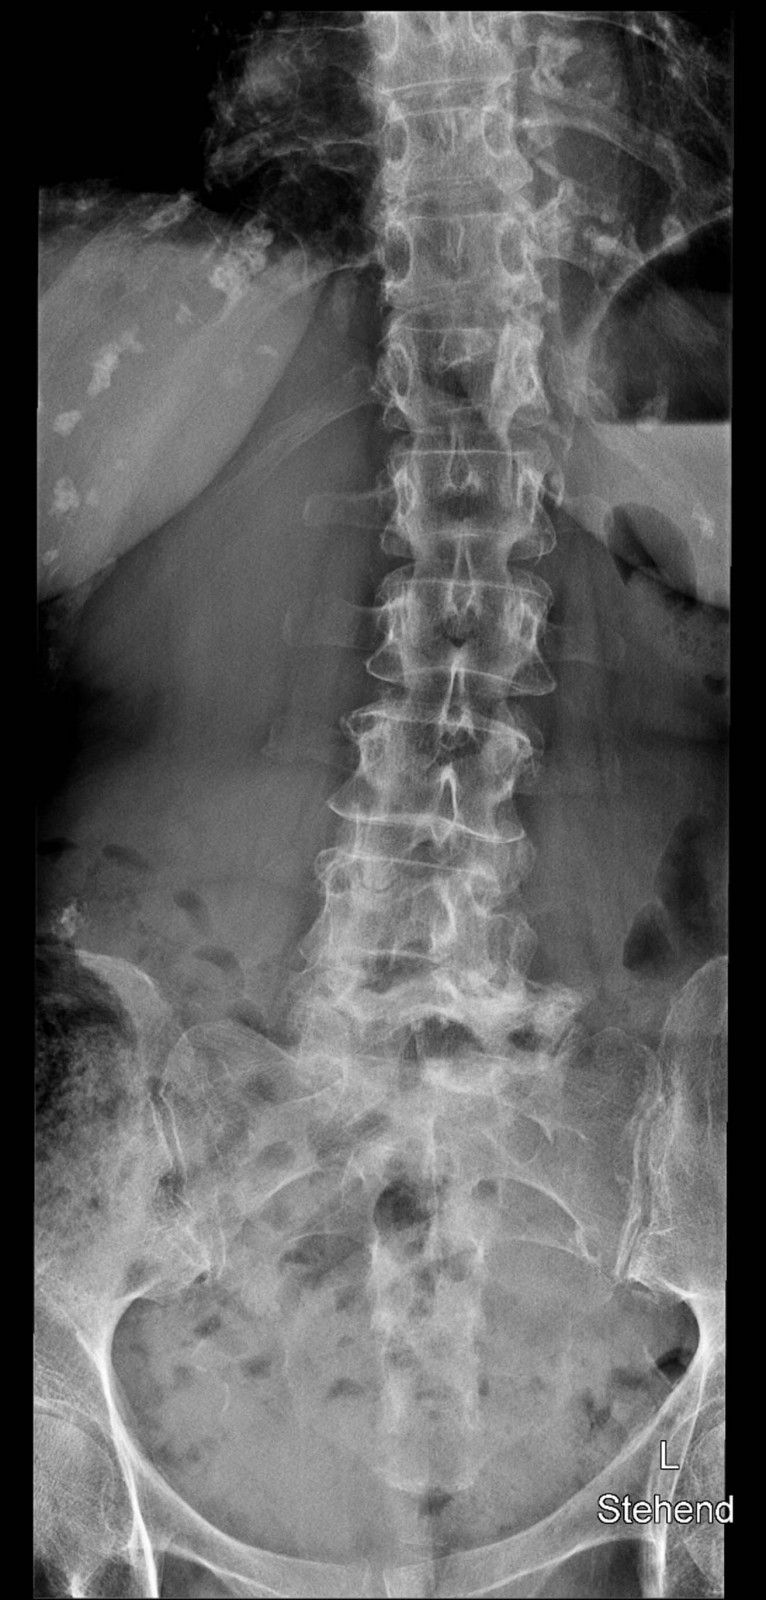

Röntgenfall des Monats März 2017 mit Auflösung

80 jährige Patientin mit chronischen linksbetonten Schmerzen lumbal am Übergang zum Becken

WS ap

Bild vergrössern